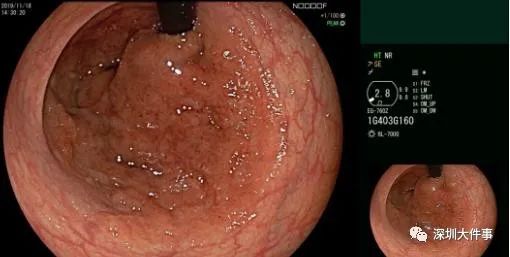

等到最近去醫(yī)院,一檢查發(fā)現(xiàn)已是腫瘤!84歲的劉女士,這幾年一直便血,最近越來(lái)越嚴(yán)重,幾乎每次都便血,并且大便里還有鼻涕一樣的黏液。家人覺(jué)得不對(duì)勁,帶她到當(dāng)?shù)蒯t(yī)院就診,檢查發(fā)現(xiàn)是罕見(jiàn)的消化道腫瘤,醫(yī)生建議她轉(zhuǎn)到南方醫(yī)科大學(xué)深圳醫(yī)院。在南方醫(yī)科大學(xué)深圳醫(yī)院,劉女士做了一次腸鏡,結(jié)果觸目驚心。劉女士的直腸九成長(zhǎng)滿腫瘤,已經(jīng)處于癌變前期。要不是老年人代謝慢,情況還會(huì)更壞。

一般的治療方法是外科手術(shù)。手術(shù)難度高,風(fēng)險(xiǎn)大,三名醫(yī)生接力輪流上臺(tái),足足花了7個(gè)半小時(shí)才把腫瘤完整剝離。腫瘤直徑達(dá)20公分,面積之大臨床罕見(jiàn)。但這種風(fēng)險(xiǎn)其實(shí)可以避免醫(yī)生表示,劉女士的腫瘤起源于大腸黏膜的隆起型病變。值得留意的是,它跟大腸癌關(guān)系密切,比息肉腺瘤具有更高的惡變潛能,多發(fā)生在直腸、乙狀結(jié)腸。但它常常容易被漏診,并且在癌變前很少會(huì)引起臨床癥狀,患者很難覺(jué)察。醫(yī)學(xué)界描述腫瘤的治療效果,有一個(gè)名詞叫“五年生存率”,指的是某種腫瘤經(jīng)過(guò)各種綜合治療后,病人生存5年以上的比例。目前我國(guó)胃癌患者的五年生存率,平均僅為37%。如果早發(fā)現(xiàn)早治療,生存率可以大大提升。但在胃癌初期,胃并不會(huì)“喊痛”。大部分患者是沒(méi)有癥狀的,僅有一小部分的人會(huì)出現(xiàn)輕度消化不良癥狀,如輕微飽脹、惡心、上腹隱痛等,這些癥狀并不典型,很容易和胃病混淆,所以更多的是被忽視。一旦病人感覺(jué)到疼痛,常排黑便,基本上已經(jīng)到了進(jìn)展期,這時(shí)候做治療,預(yù)后差,也容易復(fù)發(fā)和轉(zhuǎn)移。特別是老人家,一定要盡早開(kāi)始第一次檢查,發(fā)現(xiàn)問(wèn)題及時(shí)處理。臨床上,很多老人家就是因?yàn)殚_(kāi)始第一次胃腸鏡檢查的時(shí)間太晚,才會(huì)越拖越嚴(yán)重。因此,醫(yī)生提醒,市民一定要提高胃腸鏡檢查意識(shí)。消化道還有很多其他腫瘤,大多可防可治。胃腸鏡檢查就是發(fā)現(xiàn)早期胃腸癌的主要手段。對(duì)于高度懷疑是胃癌的患者,應(yīng)首選胃鏡,把內(nèi)窺鏡伸進(jìn)胃里,可以清楚看到里面的情況,還可以直接取病變組織進(jìn)行活檢。所以胃鏡又被稱(chēng)為“金標(biāo)準(zhǔn)”。這4類(lèi)人屬于高危